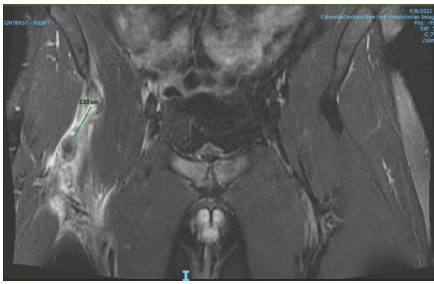

He was initially managed conservatively with physical therapy conducted by the athletic training staff. He attempted to return to football-related activities and drills when his right hip buckled again (4 weeks after initial injury). In addition to tenderness over the right hip flexor, his exam demonstrated weakness in hip flexion and knee extension. A magnetic resonance imaging demonstrated a complete avulsion of the proximal rectus femoris direct and indirect heads with approximately 3 cm of retraction in addition to FAI with associated anterior superior labral tear, osteitis pubis, and adductor aponeurosis tear (Fig. 2).

Figure 2: Coronal magnetic resonance imaging demonstrating complete avulsion of the proximal rectus femoris with approximately 3 cm of retraction.